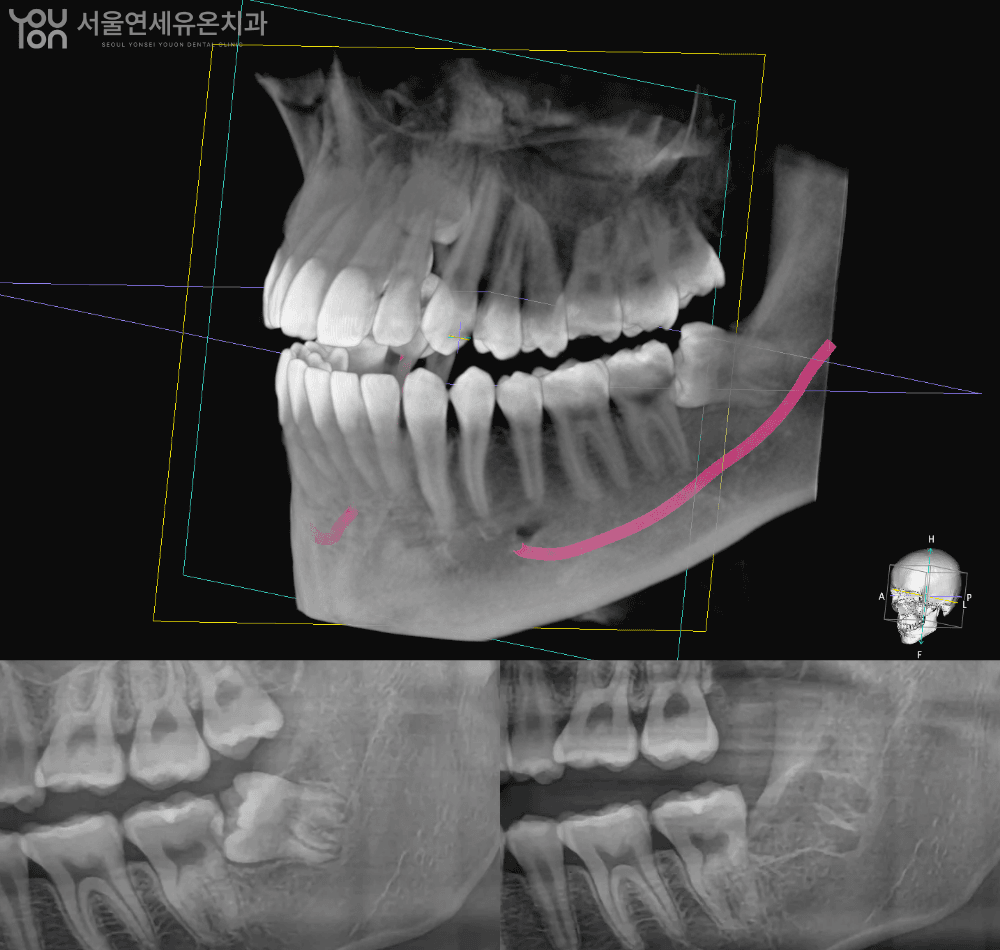

사랑니, 누구나 두렵습니다

그래서, 더 아프지 않게 준비했습니다

✔️ 통증 경감을 위한 이중 마취 시스템

✔️ 최소 절개 발치로 회복 시간을 줄이고

✔️ 정밀 진단으로 신경 손상 위험을 낮추어

시간과 건강을 모두 지켜드립니다.